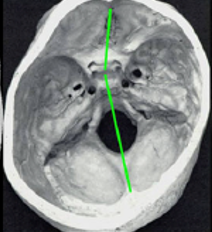

> Escafocefalia, é a sinostoses mais comum, vista mais no sexo masculino,o que acontece é o fechamento da sutura sagital levando o crânio ao formato de barco. A cirurgia é indicada de preferencia antes do sexto mês de vida, mas se a criança tiver mais idade, não impede de ser operado.